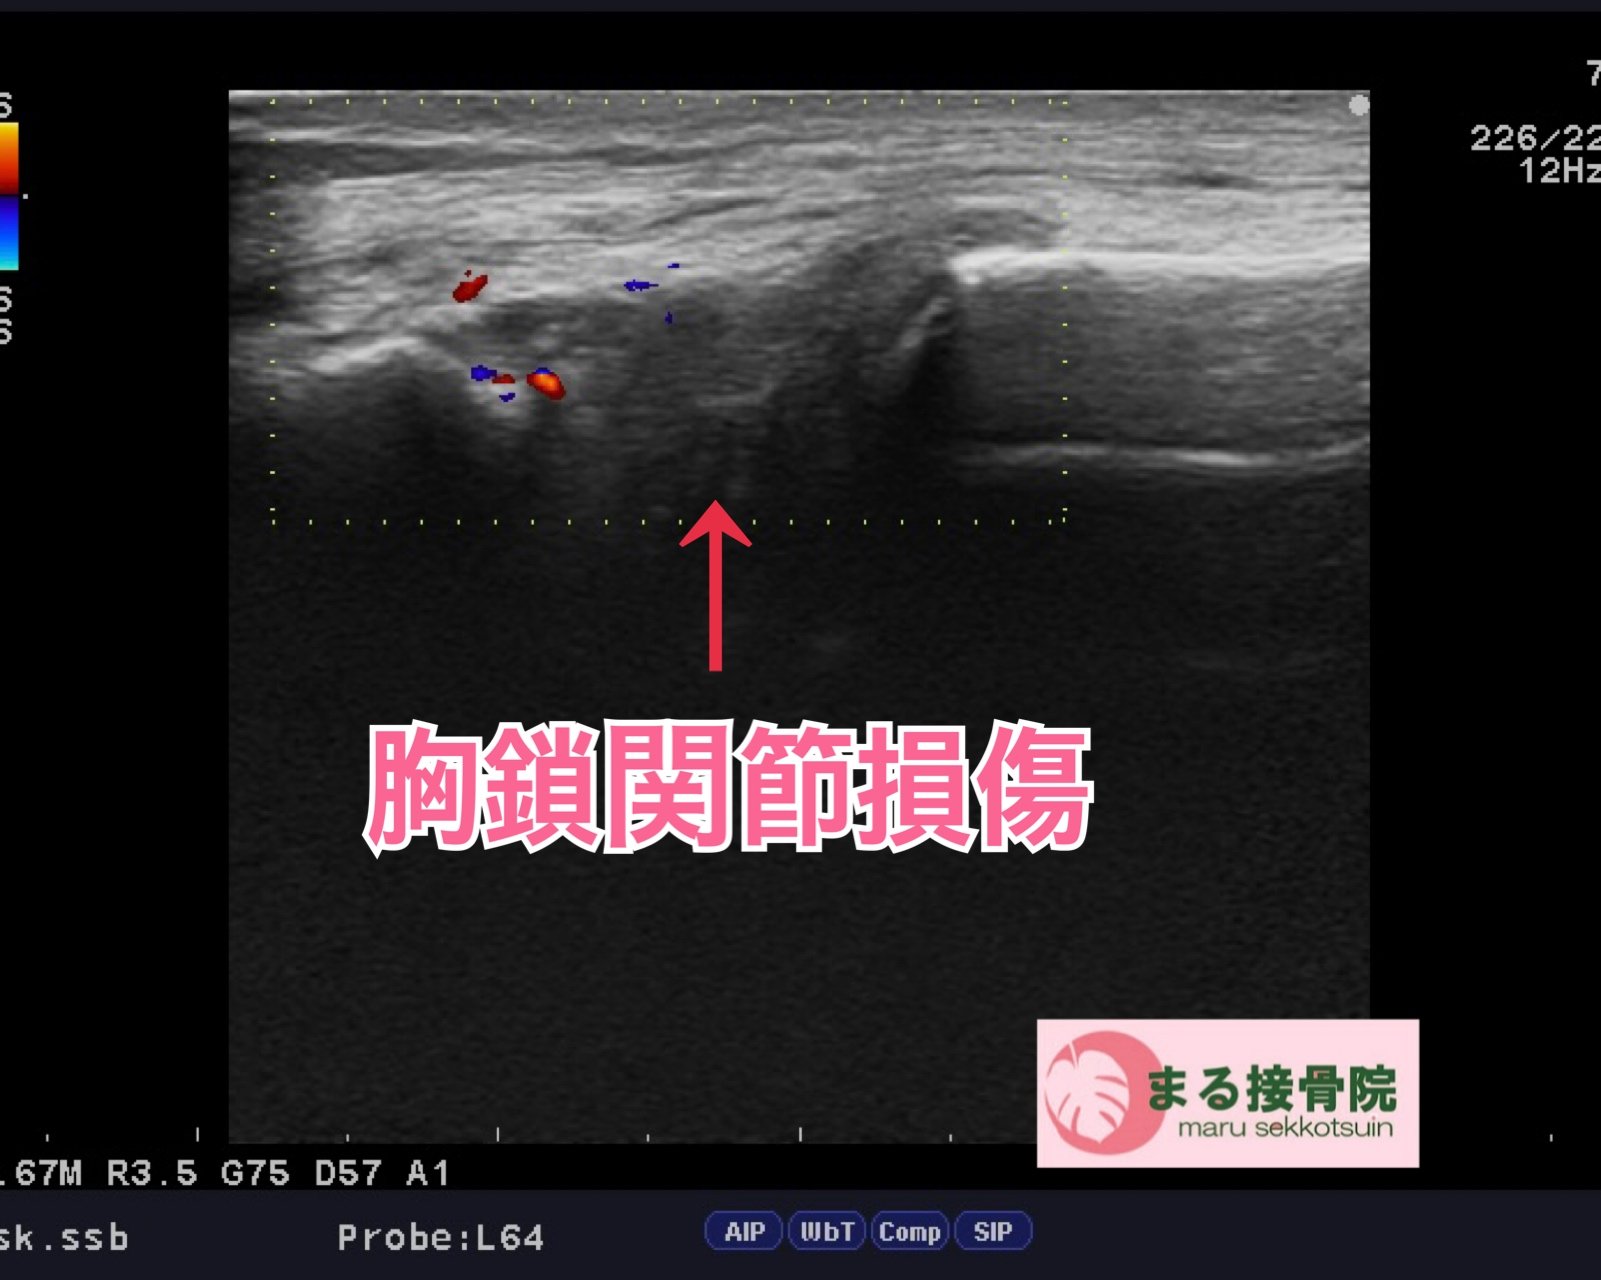

丁寧に問診・触診を行い、鎖骨に骨折は認められませんでしたが、胸鎖関節(胸の付け根と鎖骨の接合部)に強い圧痛と運動時痛が見られました。

損傷部位をより正確に把握するためエコー検査を実施したところ、結果は**「胸鎖関節損傷」**。

胸鎖関節は体の表面から触れにくく、レントゲンでは異常が分かりづらいことも多いため、エコー検査による正確な評価が非常に有効です。